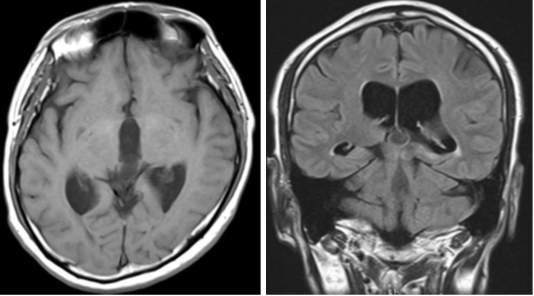

Figure 5 Postoperative magnetic resonance imaging showed the perforated area of the cyst (arrow), and third ventricle (arrowhead).

A 52-year-old man with a headache and consciousness disturbance was taken to our hospital by ambulance. He had a history of thrombocythemia and was taking aspirin. At the time of the visit, his consciousness was GCSE4V4M6, and displayed an upward gaze disorder. Computed tomography (CT) at the first visit revealed ventricular enlargement and a cyst with calcification in the pineal gland. Additionally, ventricular enlargement was visible on MRI, and a pineal gland cystic lesion with a wall thickness of 15 mm was discovered. The signal inside the cyst was lower than that of the surrounding brain parenchyma and higher than that of the cerebrospinal fluid. The cyst wall was thin and smooth, and no septal structure or nodules were discovered inside, so we diagnosed a pineal cyst. The operation was performed under general anesthesia, trepanned on the right frontal mid-pupillary line and in front of the coronal suture, and a transparent sheath was placed and a flexible scope was inserted. The cerebral aqueduct intermittently became blocked as the cyst floated in time with the cerebrospinal fluid flow. With forceps, the cyst wall was ruptured, releasing a fluid with a pale yellowish serous content. When about half of the cyst wall was removed, it was validated that the cyst had originated from the pineal gland, and the cerebral aqueduct became observable, so we decided to finish the cyst wall removal. Furthermore, we conducted an endoscopic third ventriculostomy, and pulsatile movement of the third ventricular floor was observed. The operation improved the ocular motility disorder and consciousness disorder, and the ventricles shrank on CT. Postoperative MRI revealed that the cyst wall was discontinuous, and the stoma of the third ventricle was also verified. After the surgery, the postoperative course was uneventful and he was discharged on the 8th postoperative day without complications. Ventriculomegaly was not found. on MRI six months after the operation.